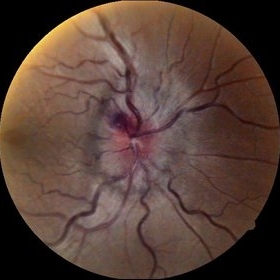

Optic Nerve Head Avulsion

Sep 15 2014 by Mehul A Shah

A 30-year-old male patient met vehicular accident and found to have optic nerve head avulsion with scarring.

Photographer: Drashti Netralaya,Dahod

Imaging device: Zeiss ff450

Condition/keywords: optic nerve head avulsion